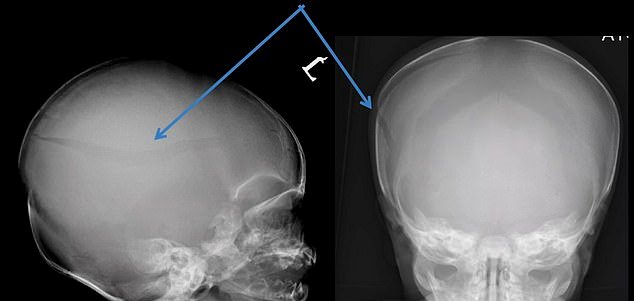

According to the police reports, Stanley died from severe injuries, including a fractured skull and brain hemorrhage, on March 28, 2017. On top of that, he suffered from several rib and limb fractures.

Prosecutor James Newton-Price QC, however, said that the evidence, including multiple bodily injuries, is convincing enough to assume that both the mother and her boyfriend disregarded the welfare of Stanley.

“This is a high culpability case. It features multiple incidents of injuries, using force and disregard for the welfare of the victim. The suffering was prolonged and there were escalating injuries, with bones broken and re-broken.